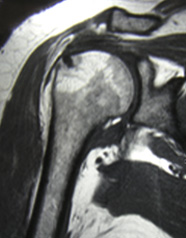

Abb 4; MRT einer Schulter nach einer Naht der Rotatorenmanschette

Magnetresonanztomografie (MRT)

Die Magnetresonanztomographie liefert 3-dimensional beurteilbare Schnittbilder mit einem sehr guten Weichteilkontrast. Sie zeichnet sich durch eine große Genauigkeit in der anatomischen Darstellung aus.

Mit Hilfe von starken Magneten und Radiowellen werden scheibchenweise Bilder der betroffenen Körperregion abgebildet. Röntgenstrahlen kommen nicht zum Einsatz wodurch es auch zu keiner Strahlenbelastung kommt. Durch die MRT gehören z.B. auch Eingriffe wie diagnostische Operationen weitgehend der Vergangenheit an. Auch für Verlaufskontrollen kommt die MRT immer wieder zum Einsatz.

Die Abb 4 links zeigt beispielsweise eine Schulter nach einer Naht der Rotatorenmanschette.